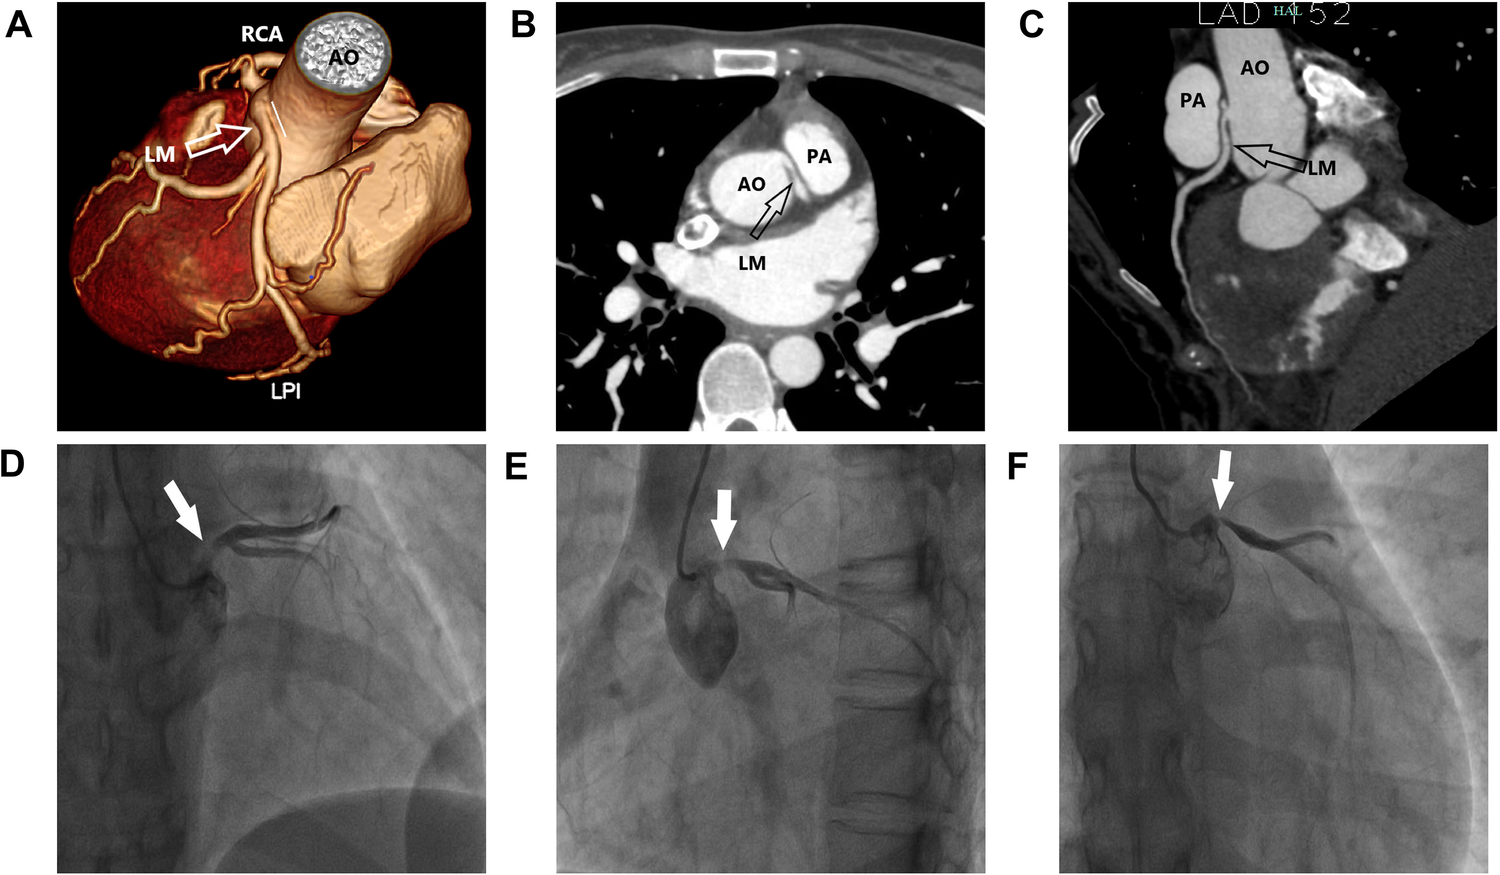

Figure 2

Clinical images. (A–C) Multiplanar reformat image showing an acute takeoff angle (<45°) of the inter-arterial left main coronary artery (LM) originating from the right coronary sinus. (D–F) Multi-angle coronary angiography showing LM originating from the upper part of the right coronary sinus, with an eccentric stenosis of 80%–90%.

With the help of ECMO, the patient's condition gradually improved and the dose of vasoactive drugs was gradually decreased. After seven days of ECMO, the patient's cardiac ultrasound still revealed a generalized decrease in myocardial contractile motion in the left ventricle; however, the LVEF had returned to 36% at an ECMO flow rate of 2 L/min. At this time, the patient's blood pressure was 112/55 mmHg, the dose of norepinephrine was 0.15 µg/kg/min, and all her organ functions were normal except for the renal function, which had not been recovered. Therefore, we decreased the flow rate of ECMO to 1 L/min. After approximately an hour, there was no considerable change in the patient's vasoactive drugs and the ECMO was discontinued. The patient was successfully weaned from the ventilator on the third day after the ECMO was discontinued. To further investigate the etiology, we improved the coronary CTA, and the image suggested that the LM originated from the right coronary sinus and traveled between the aorta and the pulmonary artery. Coronary angiography suggested that the left coronary artery originated from the upper part of the right coronary sinus, with eccentric stenosis of 80%–90% from the opening of the LM to the proximal vessel lumen, and no notable stenosis was found in the rest of the vessels (Figure 2). Therefore, we changed the diagnosis to cardiogenic shock associated with AAOCA. The patient should have undergone surgery; however, she had poor cardiac function and was in a state of malnutrition at this time (the patient's body mass index was 15.2 kg/m2). We continued to provide medication, nutritional therapy, and rehabilitation. After these treatments, the patient's cardiac function and nutritional status improved. However, early in the morning of the 10th day after the first withdrawal of VA-ECMO, the patient suffered from cardiogenic shock again and developed an intermittent third-degree atrioventricular block. The patient remained conscious and her blood pressure reached a minimum of 69/43 mmHg, requiring a high dose of vasoactive amines. Her left atrium was enlarged (LA: 41 mm) and her LVEF dropped to 28%. Since the patient's cardiogenic shock was difficult to correct, she was treated with VA-ECMO again (The initial ECMO centrifugal pump speed was 3,050 rpm which supported a flow rate of 2.63 L/min).